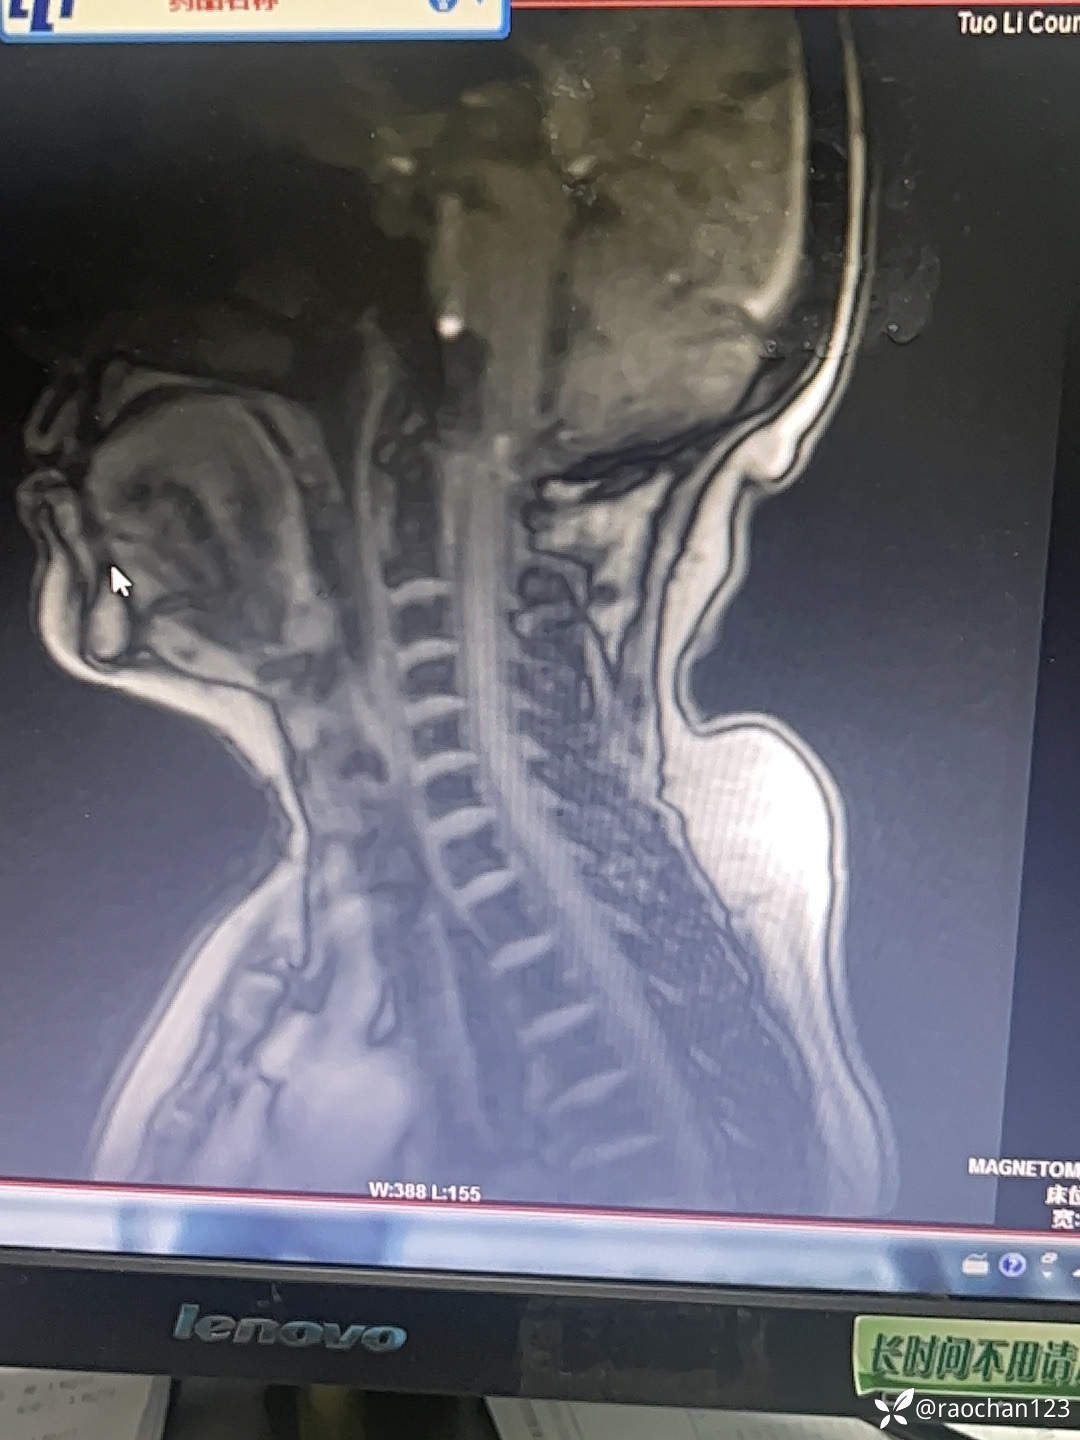

【治疗经过及结果】:给予低流量吸氧,布洛芬混悬液 解热 镇痛,左氧佛沙星抗炎(既往有头孢过敏史)、止痛,热毒宁注射液 清热解毒;艾箱灸、中药塌渍、中药涂擦、火罐、TDP、中药热奄包等中医外治通络祛痛等治疗后,仍有发热,肌酸、肌痛、关节疼痛症状。复查血常规:2024-11-8 13.93# 谷丙转氨酶 45U/L 天门冬氨酸 25U/L 白蛋白 27.0g/L 进一步查乳酸脱氢酶 284U/L 肌酸激酶 26U/L,PCT 0.44ng/ml BNP 811ng/L 免疫五项中IgGA 5.38g/L 血钙 1.94mmol/L 尿微量白蛋白 32.2mg/L 25羟基维生素D 22.68ng/ml 甲胎蛋白、癌胚抗原(-)。颈椎MRI:1.颈椎骨质增生,C4/5、C5/6、C6*7椎间盘轻度突出2、颈后皮下软组织内脂肪堆积,请结合临床。(后颈部皮下软组织内可见异常信号影,T1T2呈高信号,压脂序列呈低信号,颈椎生理曲度变直,椎体后缘连线尚连续,椎体缘骨质光滑,各椎间隙未见狭窄,椎体信号欠均匀,部分椎间盘T2信号减低,C4/5、C5/6、C6/7椎间盘向后轻度突出,硬膜囊轻度受压,椎管无狭窄,黄韧带无肥厚,颈隋未见明显异常)。骨密度:骨质疏松(T值 -4.2)。抗ANA抗体 RF 抗CCP抗体 ENA抗体谱结果待回。患者服用布洛芬混悬液后出现大汗淋漓,血钙偏低,调整为停服布洛芬混悬液、给予醋酸泼尼松10mg 2次/日 口服 解热、抗炎、止痛,金钙尔奇 600mg 2次/日,骨化三醇 0.25ug/日 口服 改善骨质量,暂给予肠内蛋白营养(患者饮食无异常),余治疗同前。